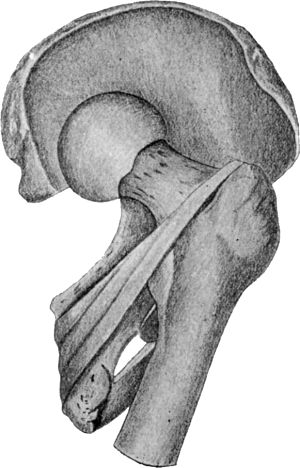

| 72. | Dislocation of Right Femur on to Dorsum Ilii | 143 |

| 73. | Dislocation on to Dorsum Ilii | 144 |

| 74. | Dislocation into the Vicinity of the Ischiatic Notch | 145 |